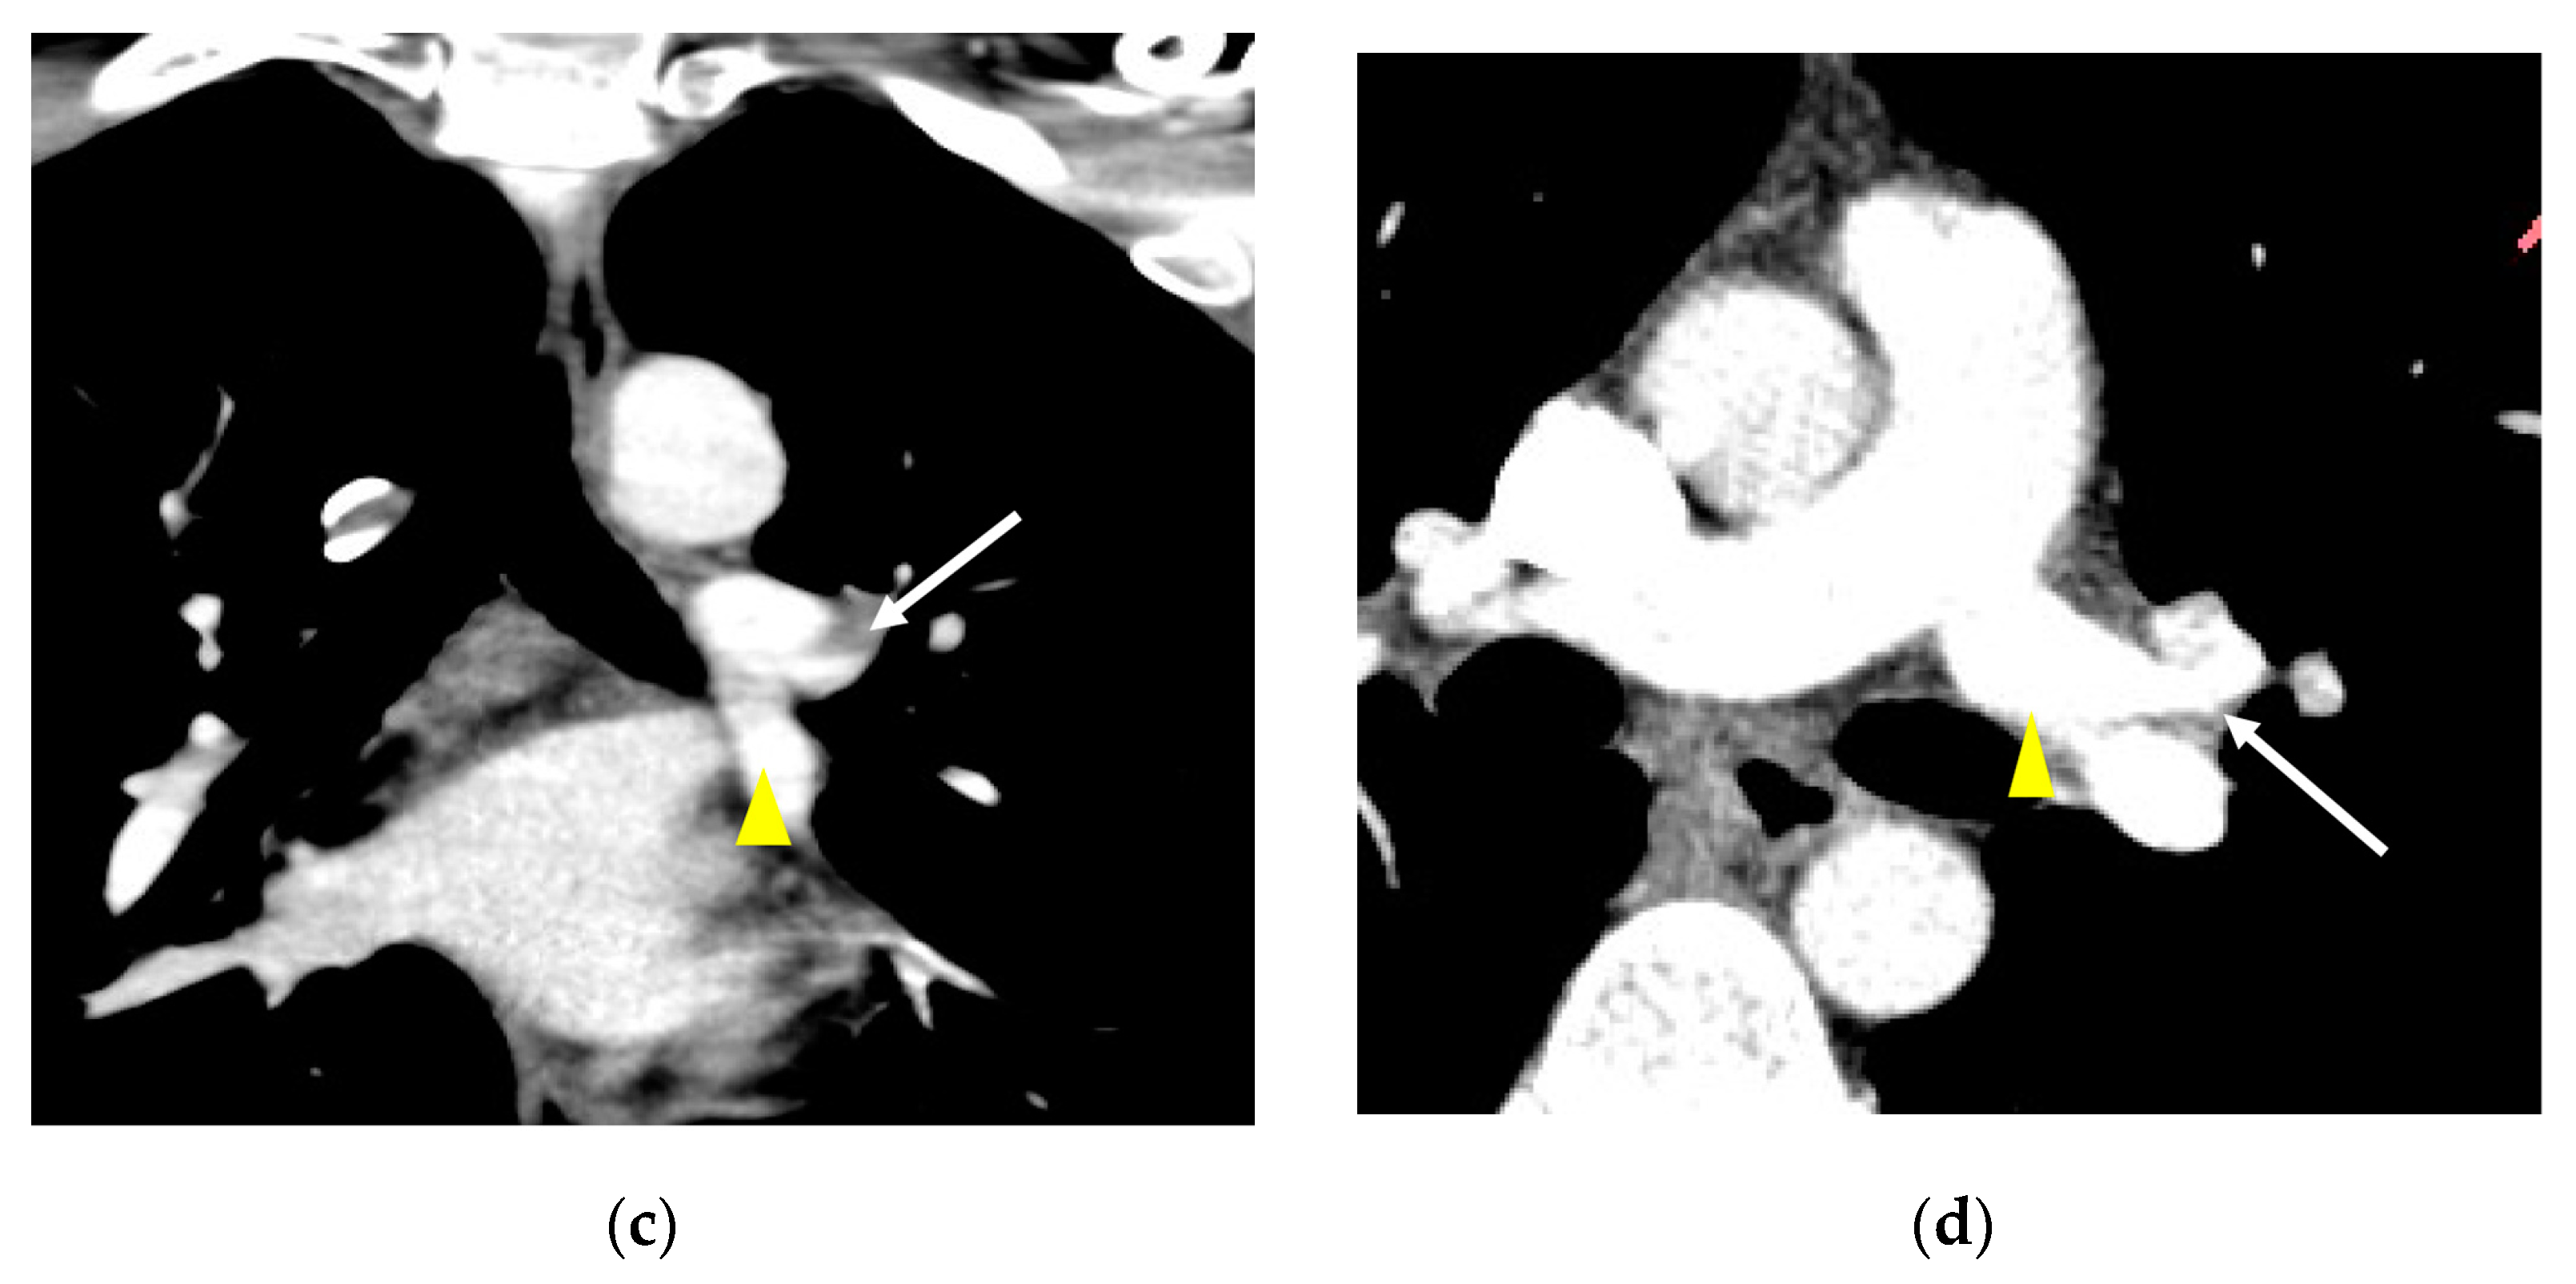

3. Results

3.2. Lobar and Segmental Supply Patternf of the AP

3.4. Presence of Other Accompanying Variations